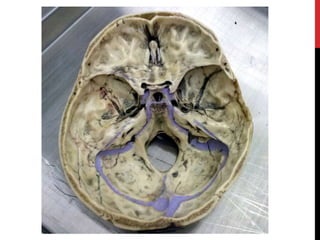

FOSAS

CRANEALES

Fosa craneal anterior

Fosa craneal media

Fosa craneal posterior

Crista Galli

Lámina cribosa

Diploe

Cresta esfenoidal

Porción petrosa del

temporal

Porción orbitaria del frontal

Surco para el

seno transverso

Protuberancia

occipital interna

seno occipital

Surco para el seno

sagital superior

Yugo del esfenoides

Fosa hipofisaria Apóf. Clinoides anterior

Apóf. Clinoides posterior

Dorso de la silla (lámina cuadrilátera)

Tubérculo de la silla

Surco prequiasmático

Cresta frontal

Agujero redondo

Agujero oval

Agujero yugular o

rasgado posterior

Fisura orbitaria

superior

(hendidura

esfenoidal)

Conducto óptico

Agujero espinoso